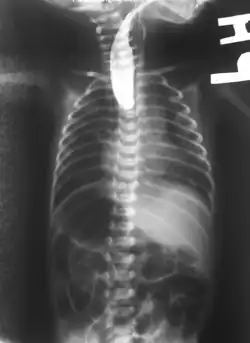

On plain X-ray, a feeding tube will not be seen pass through the esophagus and remain coiled in the upper oesophageal pouch.[11]

If any of the above signs/symptoms are noticed, a catheter is gently passed into the esophagus to check for resistance. If resistance is noted, other studies will be done to confirm the diagnosis. A catheter can be inserted and will show up as white on a regular x-ray film to demonstrate the blind pouch ending. Sometimes a small amount of barium (chalk-like liquid) is placed through the mouth to diagnose the problems. However, performing such an oral contrast study is not advised due to a risk of aspiration.[30]